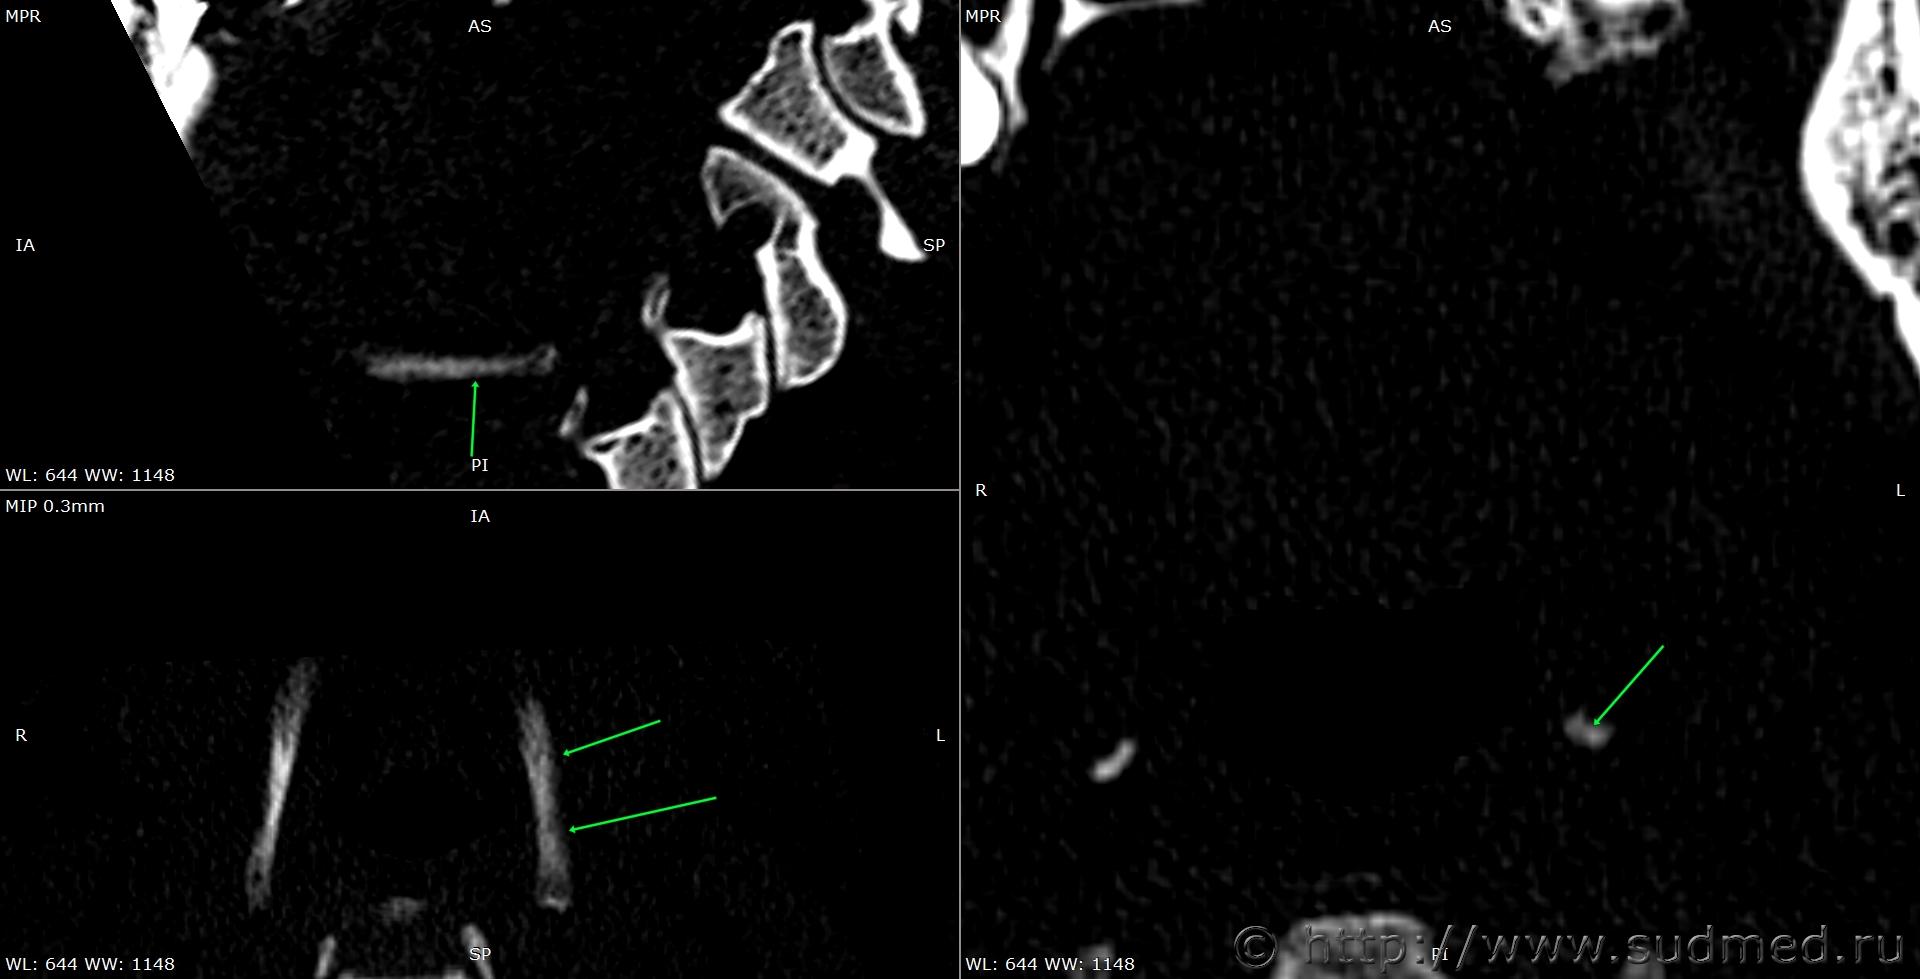

При экспертизе живого лица по медицинским документам встретились переломы шиловидных отростков височных костей. Женщина 39 лет, обратилась за медицинской помощью на 5-е сутки после травмы, тогда же провели РКТ. До этого никуда не обращалась. В протоколе РКТ отметили перелом шиловидного отростка левой височной кости, на снимках перелом на границе верхней и средней трети, дистальный отломок слегка смещен кпереди, каких-либо признаков заживления нет. Длина отростка 2,19 см. Судебная медицина - Прикрепленное изображение Также на КТ визуализируется перелом шиловидного отростка правой височной кости в нижней трети с выраженным смещением, думаю, отрывного характера (его длина 2,01 см), также без каких-либо признаков заживления Судебная медицина - Прикрепленное изображение; и гематома теменной области слева с переходом, в частности, на левую височную область, область левого сосцевидного отростка, левые околоушно-жевательную и скуловую области, левую боковую поверхность шеи Судебная медицина - Прикрепленное изображение, увеличение в объеме, нечеткость контура и разволокнение левой грудино-ключично-сосцевидной мышцы и левой ременной мышцы головы в верхней трети Судебная медицина - Прикрепленное изображение, вокруг них, в том числе кнутри от ременной мышцы, повышение плотности ПЖК Судебная медицина - Прикрепленное изображение; такие же изменения плюс повышение плотности левой подкожной мышцы шеи Судебная медицина - Прикрепленное изображение, увеличение в объеме и нечеткость контура левой околоушной слюнной железы, левая жевательная мышца не изменена Судебная медицина - Прикрепленное изображение. У подъязычной кости вижу нарушения целостности левого большого рога, но окостенение не завершено, края четко не визуализируются, поэтому о характере нарушений целостности не могу судить. Судебная медицина - Прикрепленное изображение Судебная медицина - Прикрепленное изображение В осмотрах врачей какие-либо изменения в области шеи, изменения голоса, соответствующие жалобы не отмечены; на 6-е сутки выставили острый фарингит. Помимо этой травмы есть переломы костей носа, там ничего особенного.

Пересмотрела снимки после очередного раунда чтения литературы. Справа действительно больше похоже на оссификацию связки. Слева, скорее всего, тоже есть, перелом выше подозрительной области. Судебная медицина - Прикрепленное изображение Перелом справа снимаю. Большое спасибо за наводку!

Толщина срезов 1 мм, к слову.